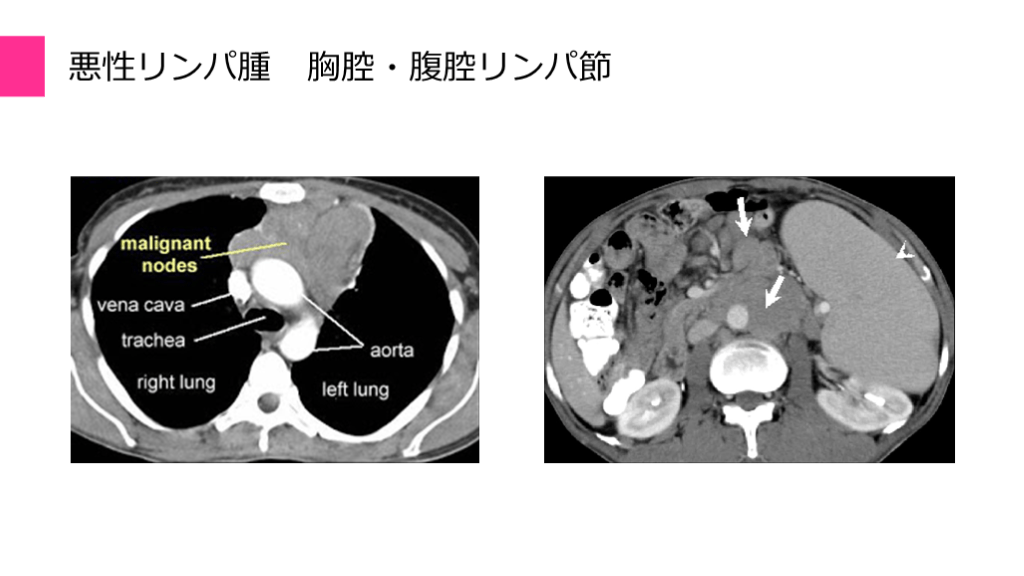

悪性リンパ腫 胸腔・腹腔リンパ節

節性 47% 節外 53% びまん性大細胞型B細胞リンパ腫の局在頻度 悪性リンパ腫 局在頻度